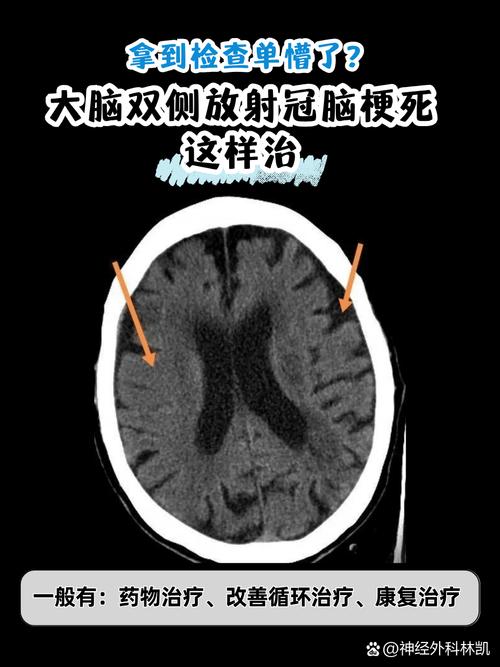

非常理解您此刻的担忧和焦虑,当CT报告显示“脑梗”时,这确实是一个需要严肃对待的信号,请不要慌张,现代医学对于脑梗已经有了一套成熟、有效的应对方案。

以下是发现脑梗后,您需要了解和遵循的核心步骤和注意事项,请务必仔细阅读。

- 头颅CT(您已经做过的):CT的主要作用是排除脑出血,因为脑梗和脑出血的治疗原则完全相反,必须先确定是缺血性(梗塞)还是出血性(卒中)。

- 头颅MRI(磁共振):这是诊断脑梗的金标准,MRI能更早、更清晰地发现梗塞的病灶,并能区分是新发的还是陈旧的梗塞。